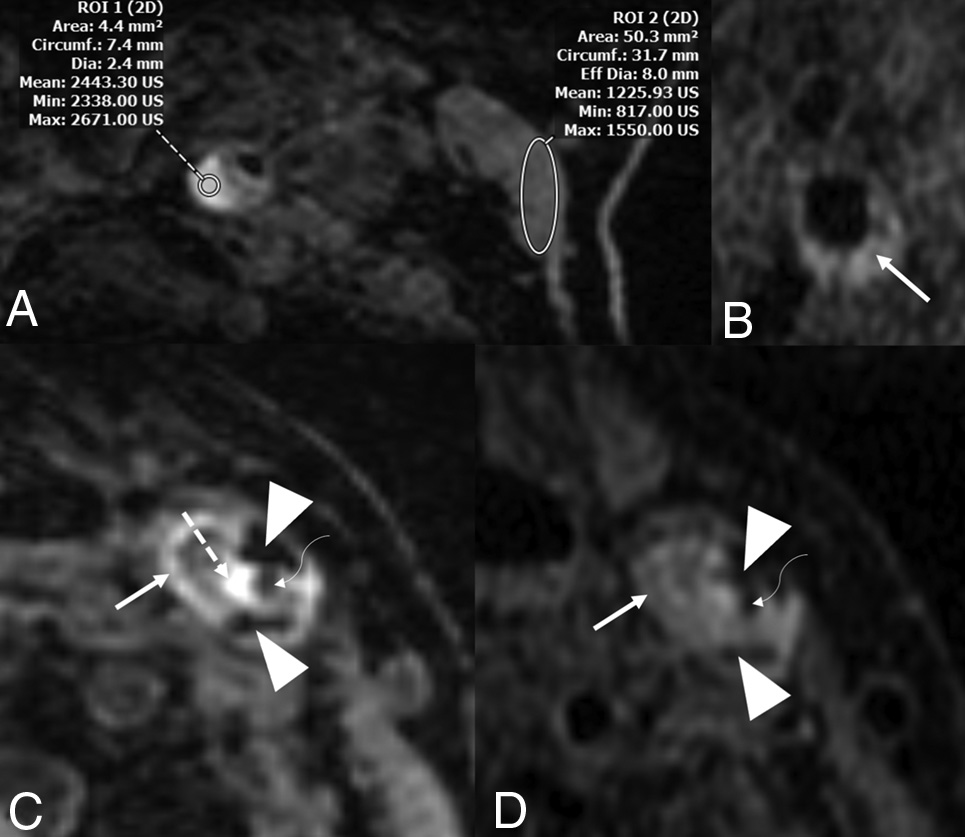

图4. ESUS患者,可能与同侧卒中相关的MR成像斑块特征。A、患者的MPRAGE显示近端ICA(左圆圈)内的高信号区域,其平均强度值为200✖️,邻近胸锁乳突肌(右圆圈)。这些发现提示存在斑块内出血。这名患者的管腔狭窄率>50%。B、另一个患者的T1 Cube(GE Healthcare)成像显示富含脂质核心的坏死核心。C、另一名患者的MPRAGE显示多种特征,包括提示周围钙化的低强度区域(短箭头)、颈动脉管腔狭窄(弯曲箭头)及临近的高强度区域(虚线箭头)和富含脂质核心的坏死核心(实线箭头)。D、与C为同一位患者/动脉显示管腔变窄(弯曲箭头)以及周围钙化(短箭头)和富含脂质核心的坏死核心(实心箭头)。斑块内出血在TI Cube成像上不如在MPRAGE序列上明显。该患者的管腔狭窄率为>50%。有强有力的证据表明,在ESUS中,斑块内出血与同侧卒中有关。在MR成像上看到的富含脂质核心的坏死核心也一直被报道具有这种相关性,尽管与斑块内出血的程度不同。